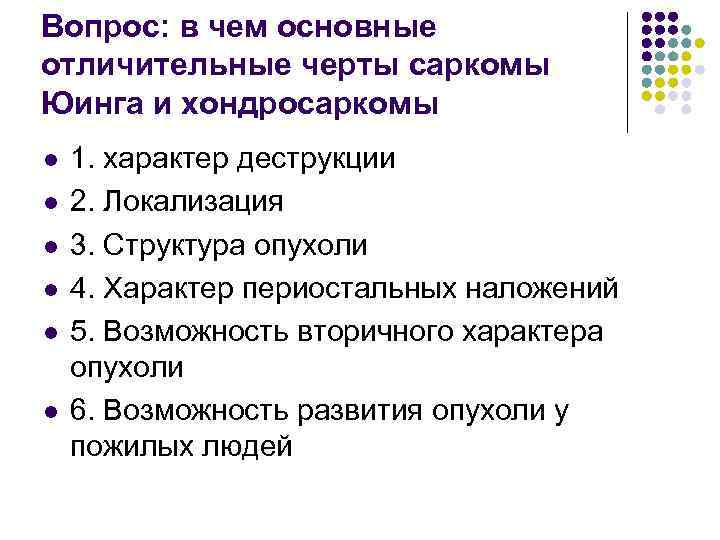

Вопрос: в чем основные отличительные черты саркомы Юинга и хондросаркомы l l l 1. характер деструкции 2. Локализация 3. Структура опухоли 4. Характер периостальных наложений 5. Возможность вторичного характера опухоли 6. Возможность развития опухоли у пожилых людей

Вопрос: в чем основные отличительные черты саркомы Юинга и хондросаркомы l l l 1. характер деструкции 2. Локализация 3. Структура опухоли 4. Характер периостальных наложений 5. Возможность вторичного характера опухоли 6. Возможность развития опухоли у пожилых людей

Ответ: l Все вышеперечисленное

Ответ: l Все вышеперечисленное